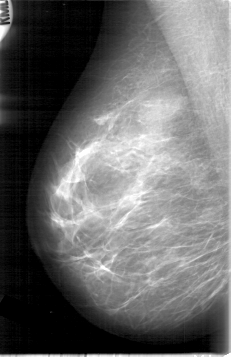

D_4006_1.RIGHT_MLO

RIGHT_MLO LINES 5341 PIXELS_PER_LINE 3451 BITS_PER_PIXEL 12 RESOLUTION 43.5 NON_OVERLAY